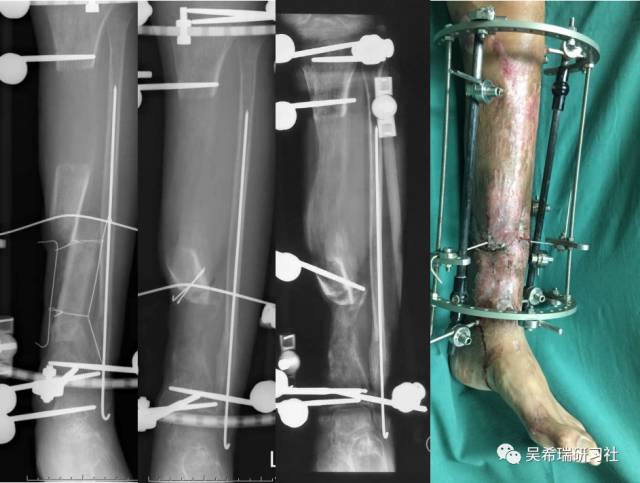

病例7

小腿骨折继发感染骨髓炎反复皮瓣9个月未下地骨质疏松继发肥胖

TIPS:9个月反复皮瓣未下地骨质严重疏松病灶清除后应用表面羟基磷灰石涂层骨圆钉半开放植骨 + 骨搬移骨水泥设计为自行吐出伤口开放换药走路骨质改善、骨愈合治疗足下垂